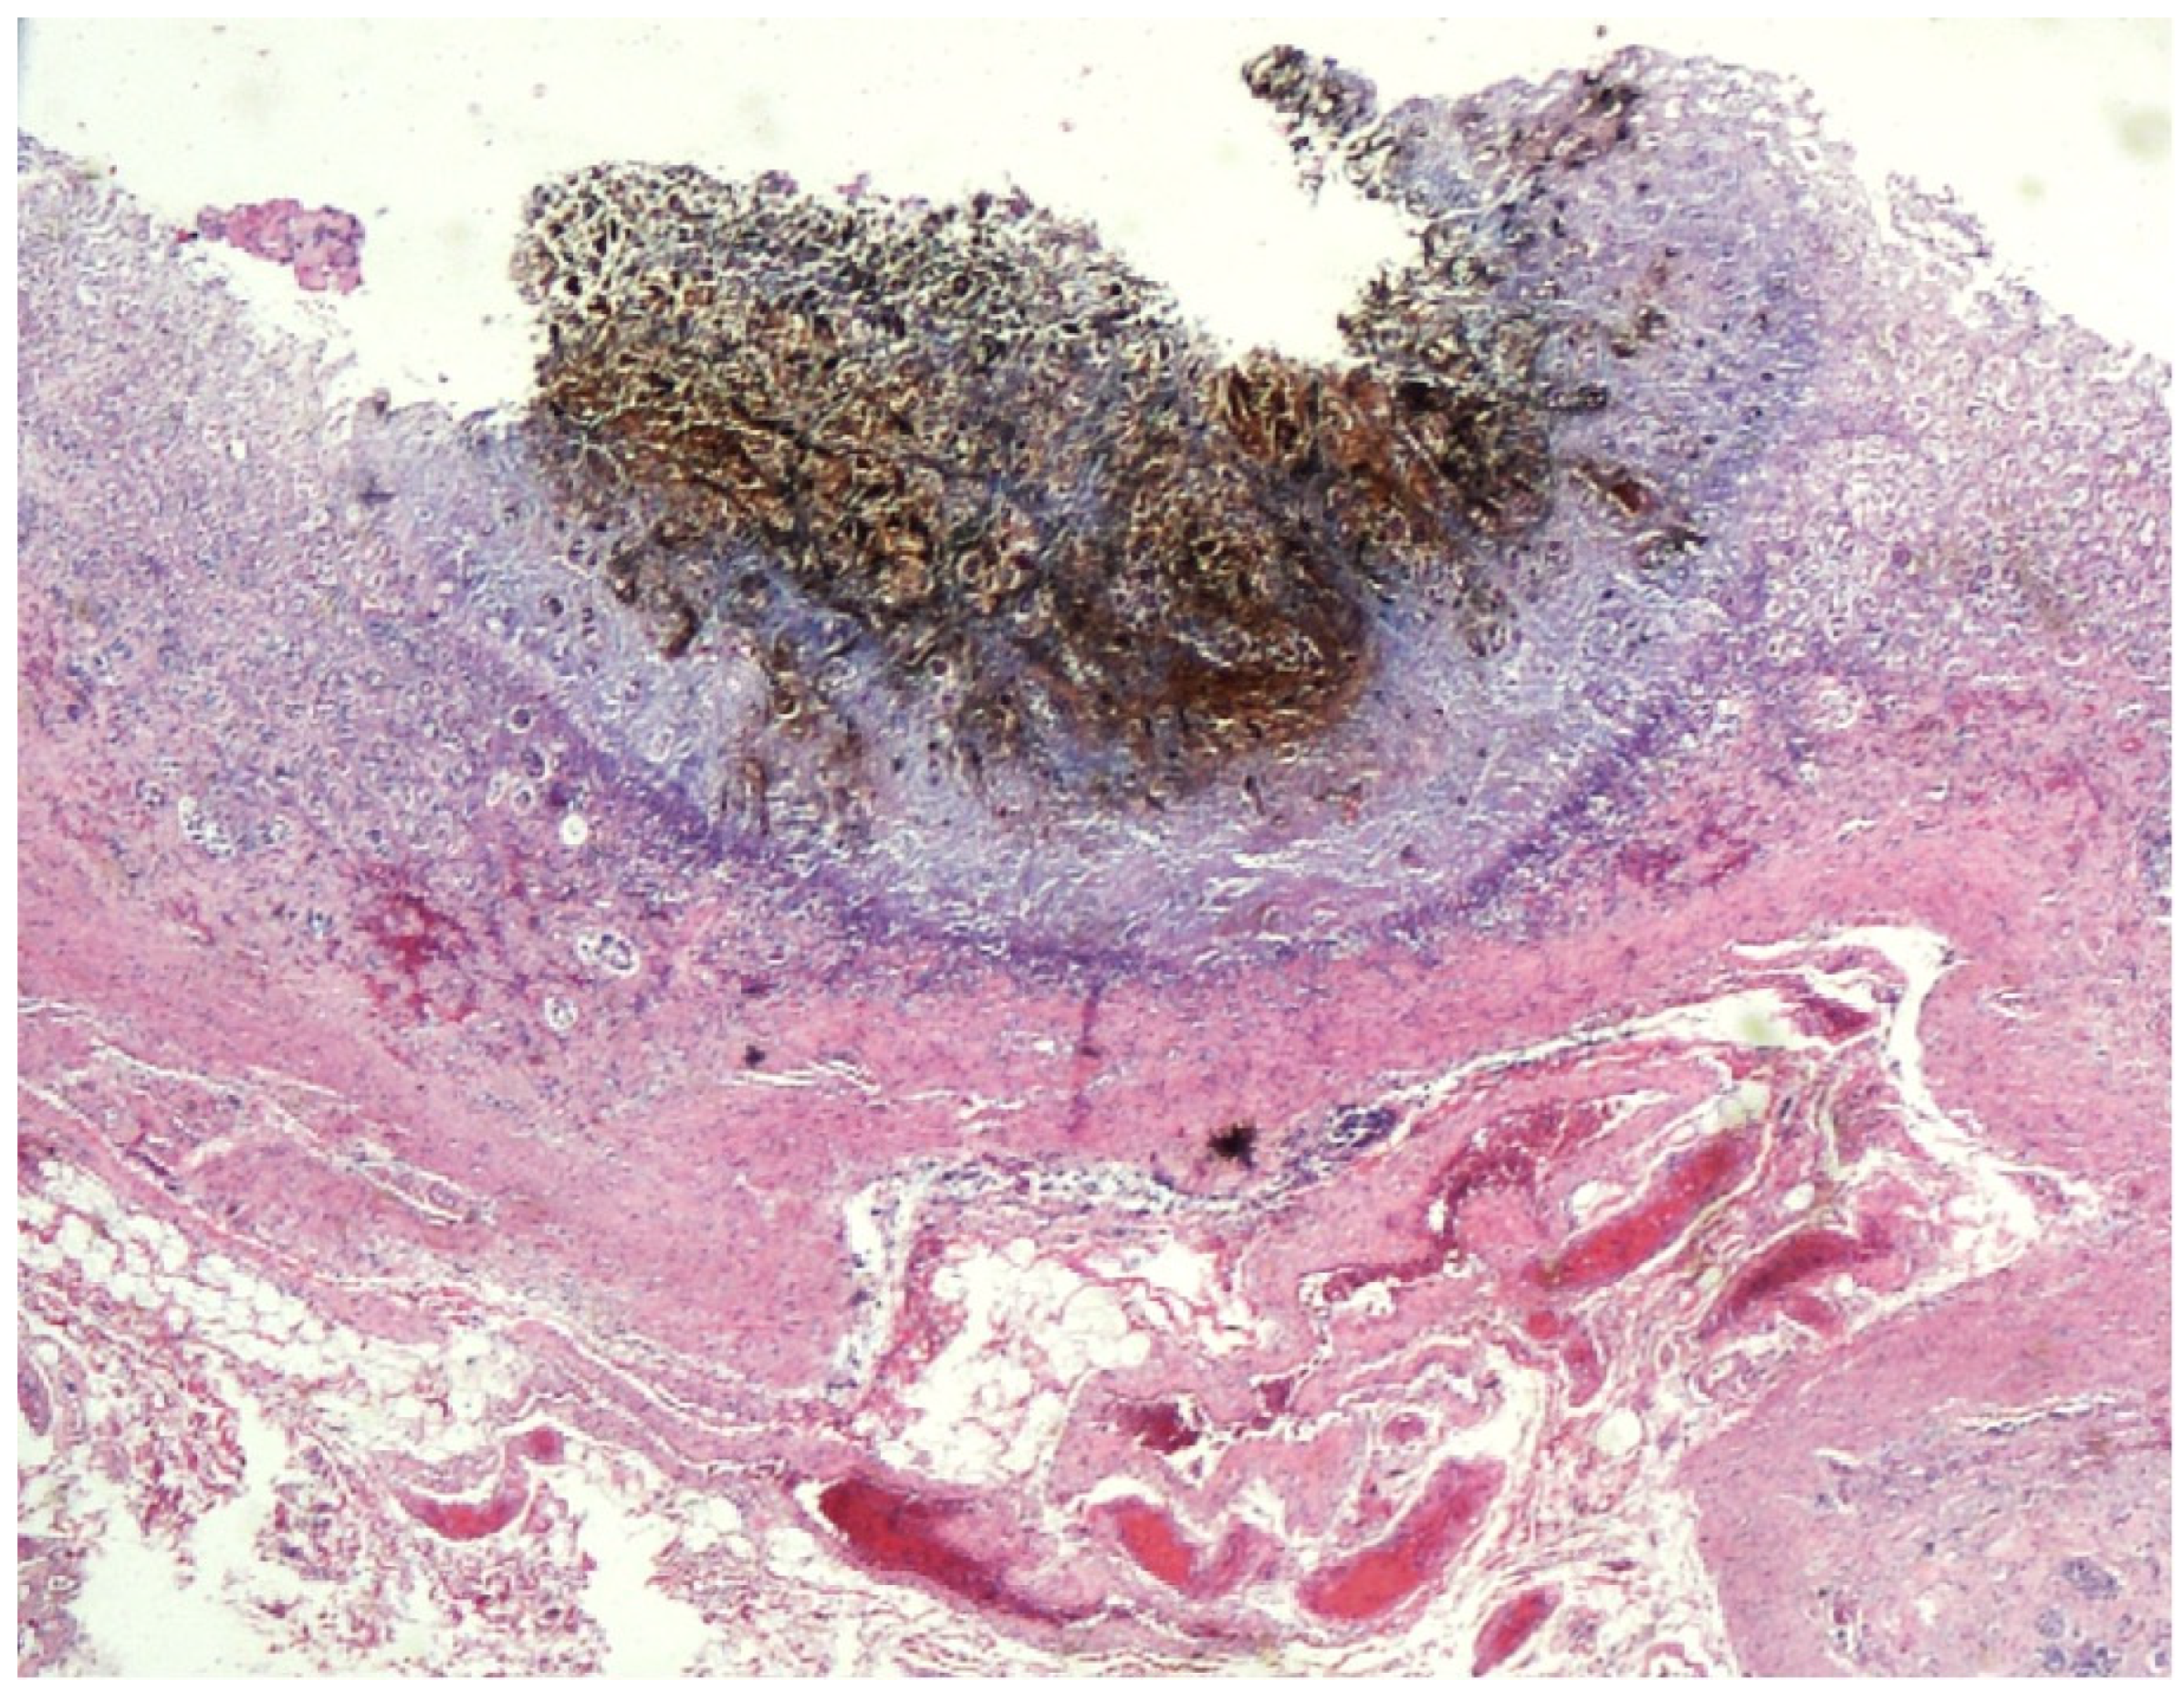

No macroscopic alterations of heart, lungs, and brain were detected. At the opening of the stomach, the presence of widespread reddish hemorrhagic spots, mostly localized in the antral region, was evidenced (Figure 6). The liver had a poorly recognizable architecture.

Microscopic observation of tissue sections stained with hematoxylin and eosin showed marked pulmonary congestion (Figure 7), micro- and macrovesicular hepatic steatosis (Figure 8), as well as vacuolization of the basal cells of renal tubules (Figure 9). Gastric wall showed edema and vascular congestion involving mucosa and submucosal layers and focal erosions of the mucosal surface consisting of necrotic foci delimitated by a dense lympho-histiocytic infiltrate (Figure 10). At the level of the skin discoloration (Figure 11), small hemorrhagic extravasations in the dermis were detected.

3.4. Polyvisceral Congestion and Wischnewski Spots

In death from hypothermia the blood is fluid, the viscera are congested, and sometimes superficial erosions or small ulcerations of the gastric mucosa, known as Wischnewski spots and due to vascular thrombosis, are observed [14].

‘Wischnewski spots’ are diffuse brownish hemorrhagic spots that are variable in size and quantity. The incidence of Wischnewski spots of the gastric mucosa in fatal hypothermia vary between 40% and 91% [15].

They are usually 1–2 mm wide, visible on gastric mucosa and, less frequently, on lower gastrointestinal tracts, and they are inconstant but pathognomonic findings of fatal hypothermia [16].

The pathogenetic mechanism underlying the Wischnewski phenomenon should be related to the erythrocyte’s autolysis and the subsequent hemoglobin release in the gastric mucosa. So, Wischnewski spots do not represent erosions or ulcerations, although in some studies even erosions are reported and the histological analysis allow to highlight the major aspects of the autolytic phenomenon. No inflammatory infiltrates or fibrin exudates are shown. Histological and immunohistochemical analyses are the major techniques to support the cause of death [17]. In the present case, although it was not possible to undergo immunohistochemical analysis, the histological findings confirm the presence of an erosion at the level of the macroscopic Wischnewski spots. This finding also suggests that other studies with large samples are needed to settle the issue of the real origin of these spots also because even the relevant literature is not one-sided on this theme: some studies concluded for erosion, others for the absence of it [17,18].

Figure 6. Stomach with widespread reddish hemorrhagic spots.

Figure 10. Gastric wall with focal erosions of the mucosal surface.